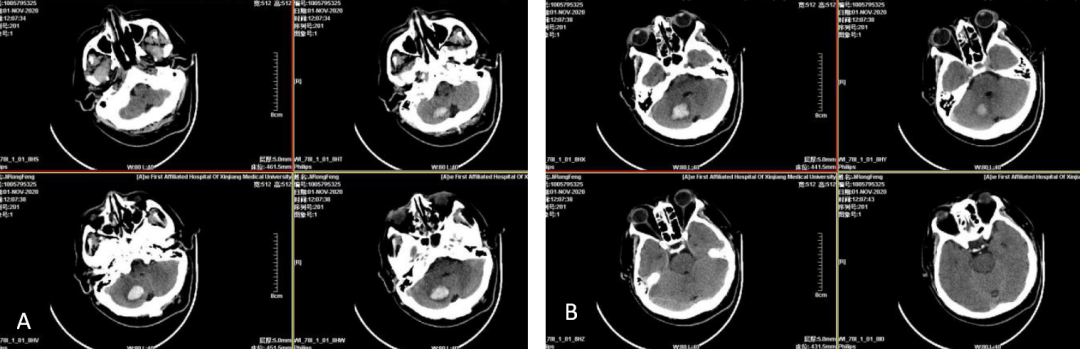

患者为小脑出血,入院后进一步行CTA及DSA检查发现左侧前交通复合体动脉瘤、左侧大脑中M1分叉部动脉瘤,小脑出血(2.5cm×2.8cm×2.4cm/2)为8.4ml,患者无神经功能恶化或脑干受压,根据2019年中国蛛网膜下腔出血指南“出现神经功能恶化或脑干受压的小脑出血者,无论有无脑室梗阻致脑积水的表现,都应尽快手术清除血肿(Ⅰ级推荐,B级证据);不推荐单纯脑室引流而不进行血肿清除(Ⅱ级推荐,C级证据)”[13],患者无蛛网膜下腔出血,结合动脉瘤位置[前交通动脉、大脑中动脉,破裂出血常在纵裂池、环池、鞍上池、四叠池、外侧裂以及相近的脑实质内(常位于幕上)]及小脑出血(幕下,位于小脑脑实质内)特点,小脑出血与动脉瘤无关,所以脑出血可选择保守治疗,密切观察患者的症状、体征、意识、瞳孔及复查CT结果,若有病情进展,可考虑手术。